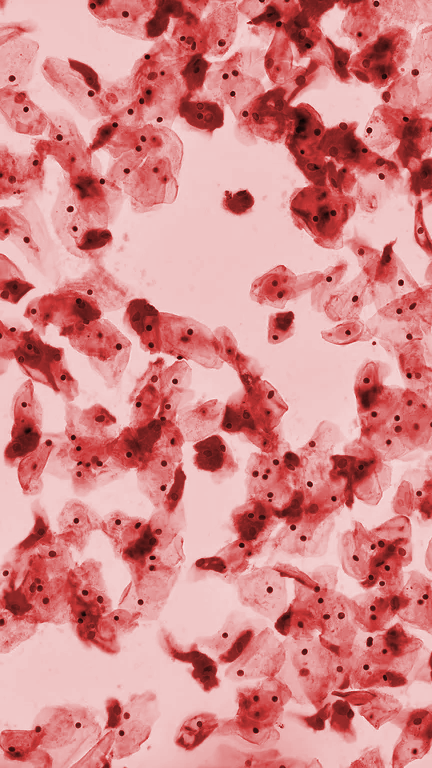

Citología

Prueba de mayor precisión y confiabilidad que el papanicolaou tradicional que permite la detección temprana de alteraciones del cuello uterino. Los informes se emiten siguiendo el protocolo de Bethesda.

Tipo de muestra: Muestra de células del cuello uterino y del canal endocervical que se recogen utilizando un pequeño cepillo de plástico que preserva el 100% de la muestra recolectada la cual se coloca en el recipiente de Base Líquida para ser enviada al laboratorio para estudio. Se deben indicar datos de edad, fecha de última regla e historia clínica para un estudio óptimo.

Prueba citológica tradicional que permite la detección temprana de alteraciones del cuello uterino. Los informes se emiten siguiendo el protocolo de Bethesda.

Tipo de muestra: Muestra de células del cuello uterino y la vagina obtenidas mediante una espátula, extendidas y fijadas sobre una lámina. Se deben indicar datos de edad, fecha de última regla e historia clínica para un estudio óptimo.